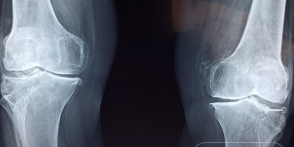

4. 퇴행성 관절염과 류마티스 관절염 초기 증상 차이

퇴행성 관절염과 류마티스 관절염은 비슷한 증상을 보일 수 있지만, 원인과 치료 방법에서 차이가 있습니다. 퇴행성 관절염은 연골의 마모로 발생하며, 주로 무릎, 엉덩이, 허리 등 큰 관절에 영향을 미칩니다.

반면, 류마티스 관절염은 자가 면역 질환으로 작은 관절에 영향을 미치며, 염증과 붓기, 발열 등의 증상이 동반됩니다. 초기 증상 차이를 인식하는 것이 중요하며, 정확한 진단을 받기 위해 병원을 방문하는 것이 필요합니다.